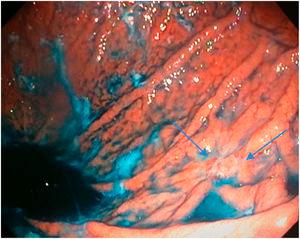

Mean duration (minutes) of the mucosal examination was significantly longer with SACE (12.8 ± 2.6, 95% CI: 12.09-13.51 versus 9.6 ± 2.42, 95% CI: 8.88-10.31; p = 0.0001) (Table 2). Endoscopic findings (histologic confirmation): 18% (9/50) of the patients had normal mucosa, 20% (10/50) had chronic gastritis associated with H. pylori, 6% (3/50) had reactive gastritis, and 56% (28/50) had chronic gastritis. Six cases of intestinal metaplasia with no dysplasia (figs. 2 and 3) and one case of poorly differentiated adenocarcinoma (diffuse, according to the Lauren classification) that presented as a flat, ulcerated lesion (fig. 4, Table 3) were detected. The detection rate for premalignant lesions and gastric cancer was 14%. The most frequent region and areas with lesions were the antrum and lesser curvature. Sensitivity (Sn), specificity (Sp), positive predictive value (PPV), negative predictive value (NPV), and diagnostic accuracy were 100, 95, 80, 100, and 96%, respectively, for SACE. Sn, Sp, PPV, NPV, and diagnostic accuracy were 100, 45, 20, 100, and 52%, respectively, for conventional endoscopy. SACE was superior to conventional endoscopy for detecting pre-neoplastic lesions (p = 0.03; OR = 12) (Table 4). Interobserver agreement was low (kappa 0.4).

Chromoendoscopy and biopsyThe studies were performed by physicians in endoscopy training and supervised by staff physicians. In the SACE group, images were taken upon entrance, after completing additional cleansing of the gastric chamber (if necessary) to expose 100% of the mucosa, following the previously described coding (Table 1, fig. 1). Premalignant lesion was defined as a lesion having any of the following characteristics: polypoid or ulcerous, Paris 0-IIa and 0-IIc lesions, change in coloring (reddish or whitish), or markedly altered flat, pale mucosal areas. If any lesion was suspected of being premalignant, 0.3% indigo carmine was sprayed on it and biopsies were taken. They were immediately fixed in 10% formaldehyde and evaluated by hospital pathologists. If no premalignant lesions were suspected, but there were signs of chronic gastropathy (diffuse antral gastritis, diffuse corporal atrophic gastritis, or multifocal atrophic gastritis), systematic biopsies were taken, according to the Sydney protocol.12